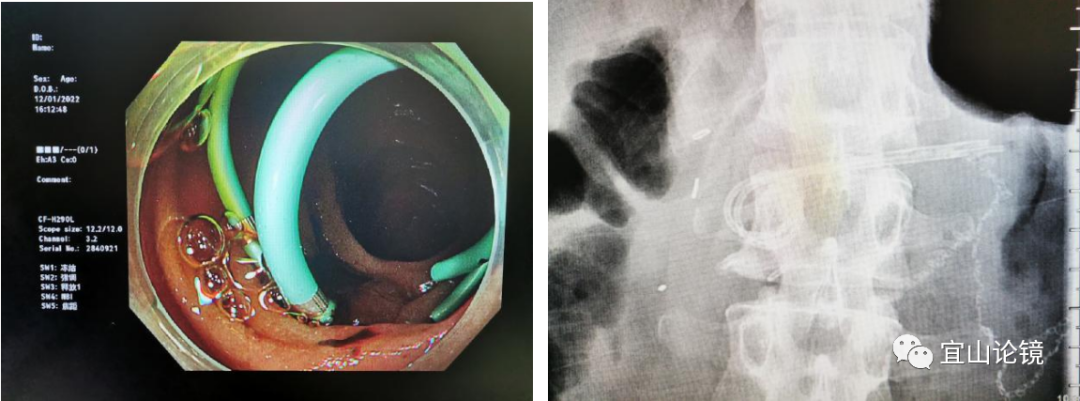

5)考虑放置2枚5F支架。导丝留置,再进反转刀,但导丝牵引吻合口方向过平,切开刀不能对点对线,只能先放一枚5F支架,再进反转刀超选。难点是刀抵住上一个支架处很难固定,极易滑开,需要耐心超选。可考虑副乳头插管方法,将导丝头探出切开刀,以导丝前端引导切开刀对点,最终第二根导丝进入胰管,切开刀跟进扩张,放置第2枚5F-5CM支架结束。

4. 胆肠吻合口

退出镜身时在胰肠吻合口近侧约10cm发现胆肠吻合口,可见吻合口通畅。术后X线定位观察无异常气体,结束手术。